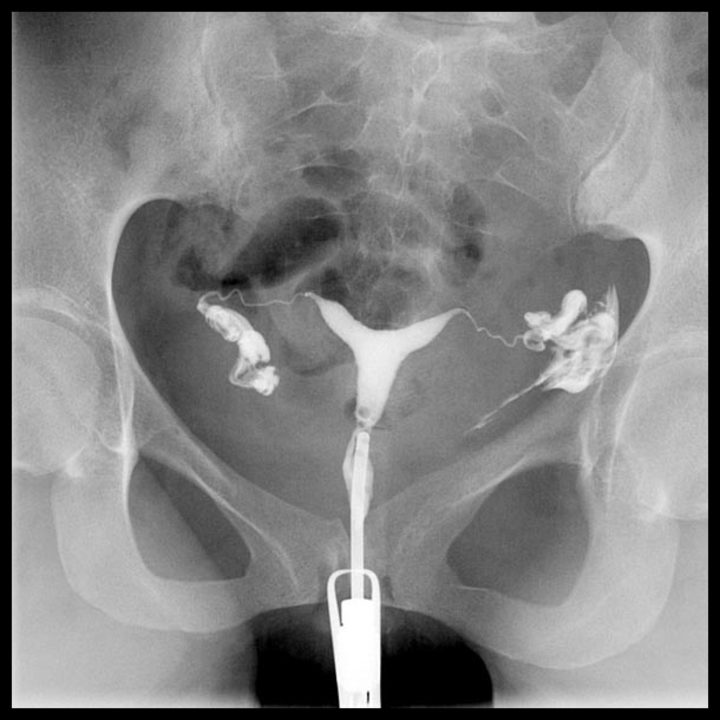

Rahim filmi (HSG) sonrası kanama olur mu?

rahim filmi çektim kanama oldu,rahim filmi sonrası kanama olanlar,rahim filmi sonrası komplikasyonlar,rahim filmi sonrası yaşanan durumlar,rahim filmi hakkında bilgiler